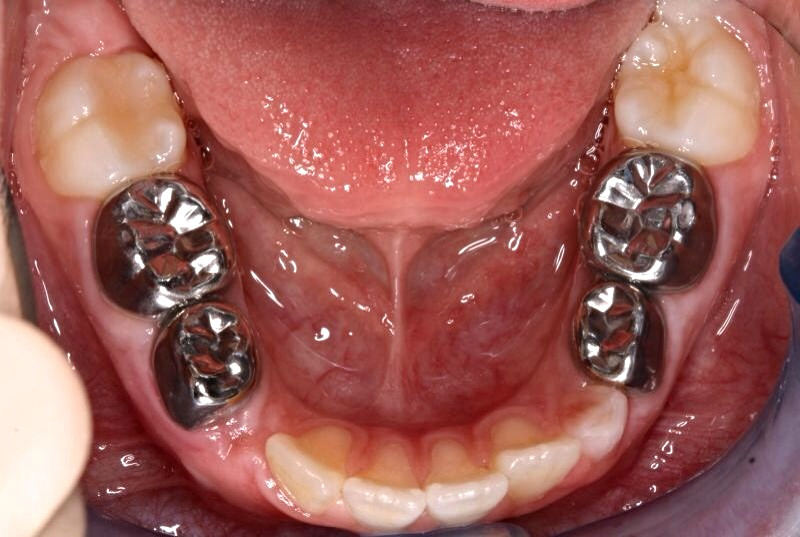

Stainless Steel Crowns

Stainless steel preformed crowns are used to cover the decayed tooth and provide the chewing efficiency, prevent spread of decay and to maintain the space till the permanent counterpart erupts